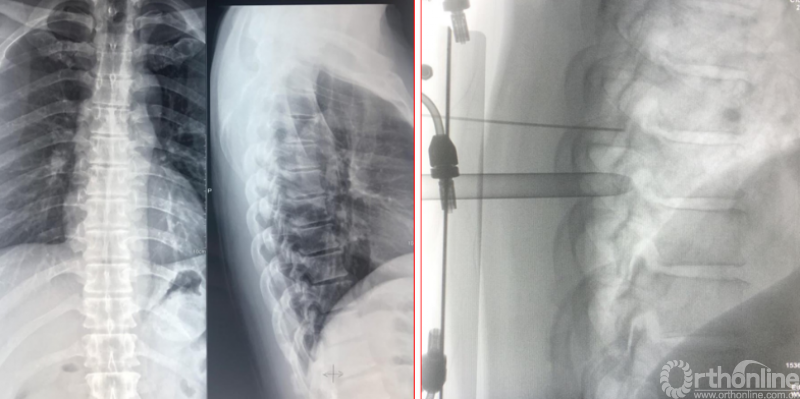

Case2:胸椎黄韧带钙化可视化的治疗

术前诊断及评分

JOA评分:3分

ASIA等级:C级

诊断:

1:多节段胸椎黄韧带骨化症双下肢不全瘫

2:腰椎内固定术后

3:Ⅱ型糖尿病

术前资料

术后病情评估

术后第二天JOA评分:6分;RR:37.5%(可);ASIA等级:D级。

术后第二天资料

术后影像学资料